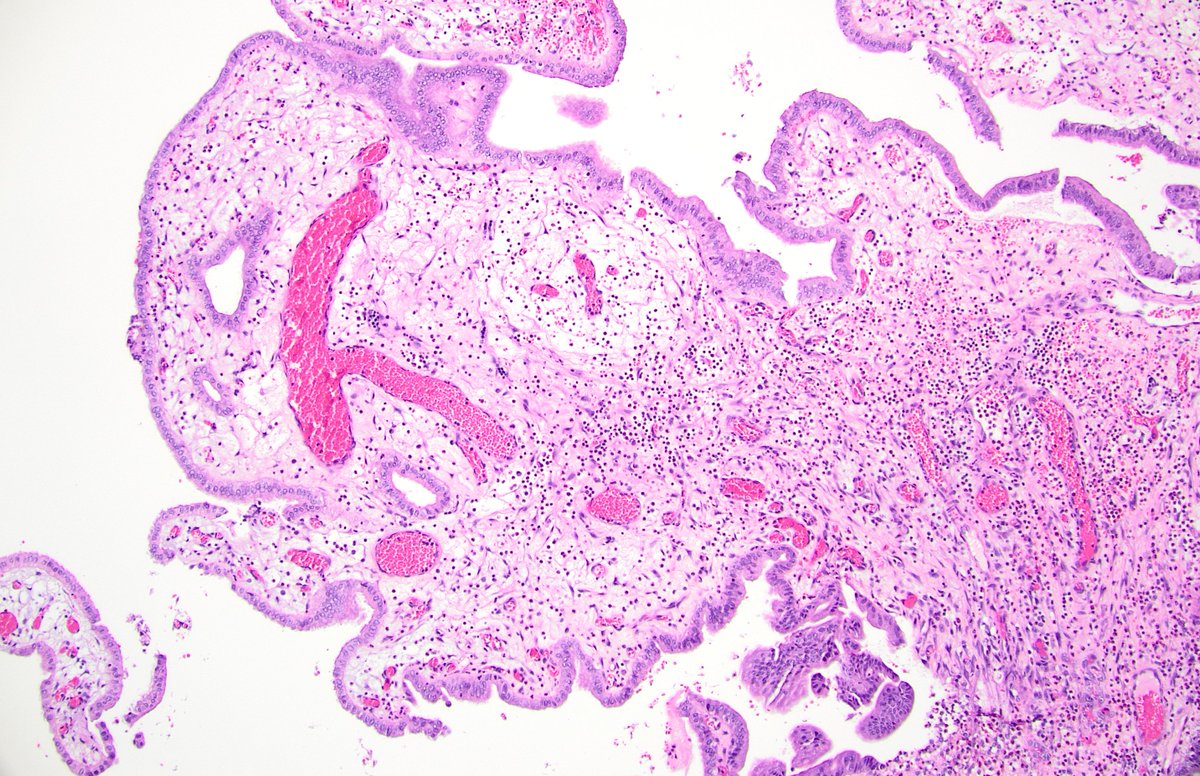

@forthejon @et565 On morphology I would have gone for HG dysplastic naevus. PRAME and molecular seem to point in the same direction here and what you have said is v reasonable. Management is the same - wider excision.

#WhatsNewInDermpath Utilizing PRAME expression and a meta-analytic framework for iSALT to explore atypical late-onset nevi of the elderly and their relationship with lentiginous and nested nevoid melanomas journals.lww.com/amjdermatopath…